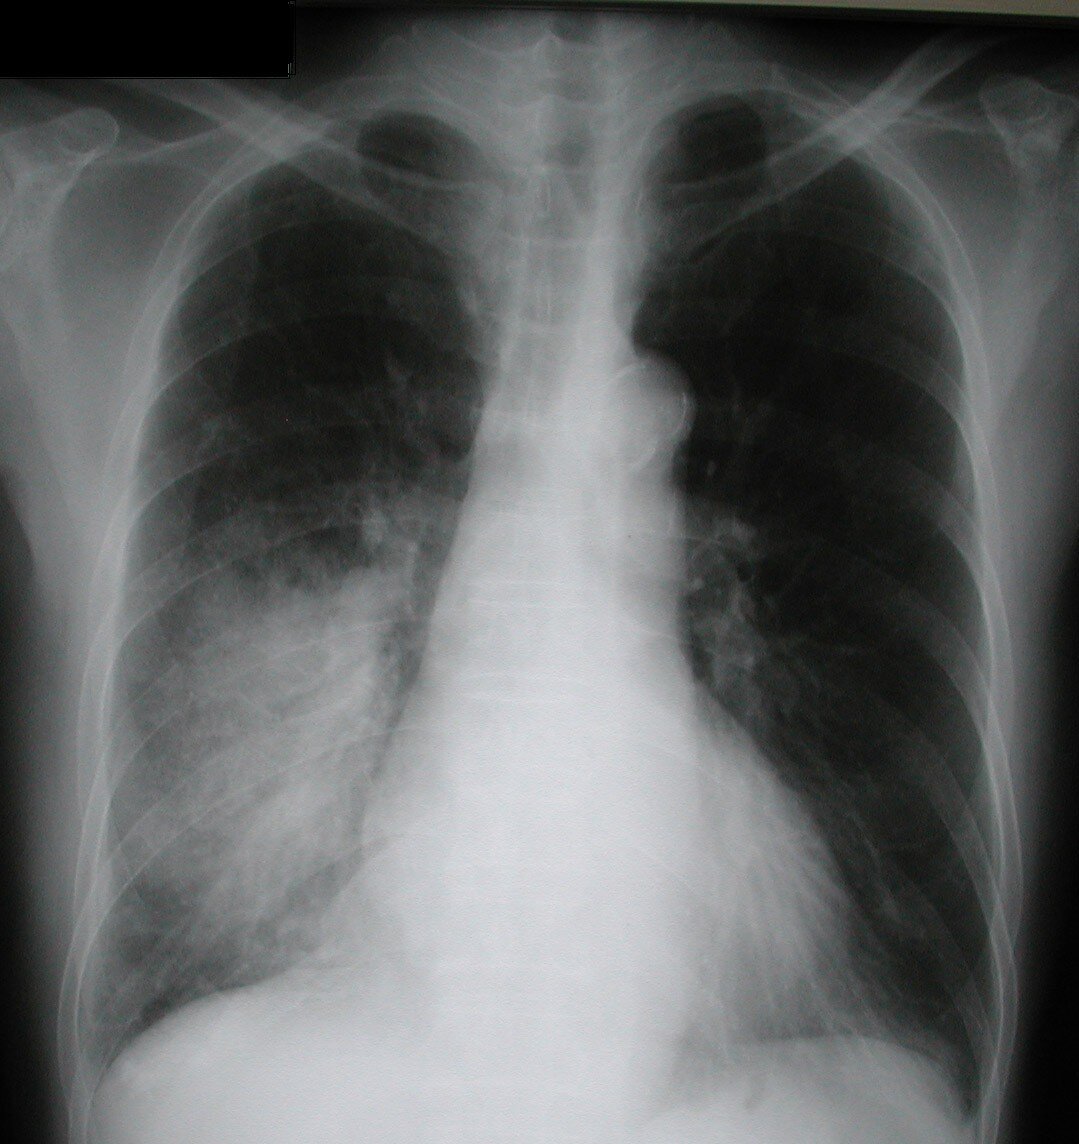

Фото из интернета.